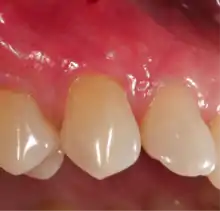

A free gingival graft is a dental procedure where a small layer of tissue is removed from the palate of the patient's mouth and then relocated to the site of gum recession. It is sutured (stitched) into place and will serve to protect the exposed root as living tissue. The donor site will heal over a period of time without damage. This procedure is often used to increase the thickness of very thin gum tissue.

A subepithelial connective tissue graft takes tissue from under healthy gum tissue in the palate, which may be placed at the area of gum recession. This procedure has the advantage of excellent predictability of root coverage,[20] as well as decreased pain at the palatal donor site compared to the free gingival graft. The subepithelial connective tissue graft is a very common procedure for covering exposed roots.